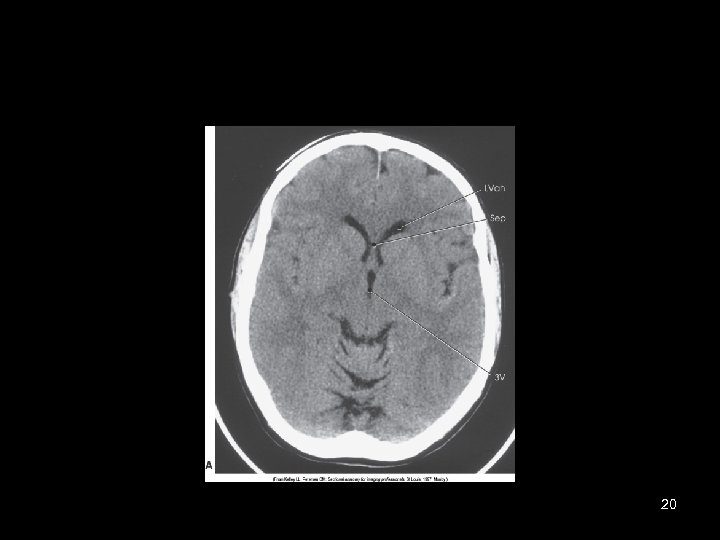

20

Diagnostic Applications • Most common anatomy examined is – Head, chest and abdomen • Exam of choice for: – Head trauma – CVA • Also useful for: – – – – – Infarctions Hemorrhage Disk herniations Craniofacial fractures and tumors Cancers Hydrocephalus Degenerative diseases Inflammatory infections Congenital disorders 52